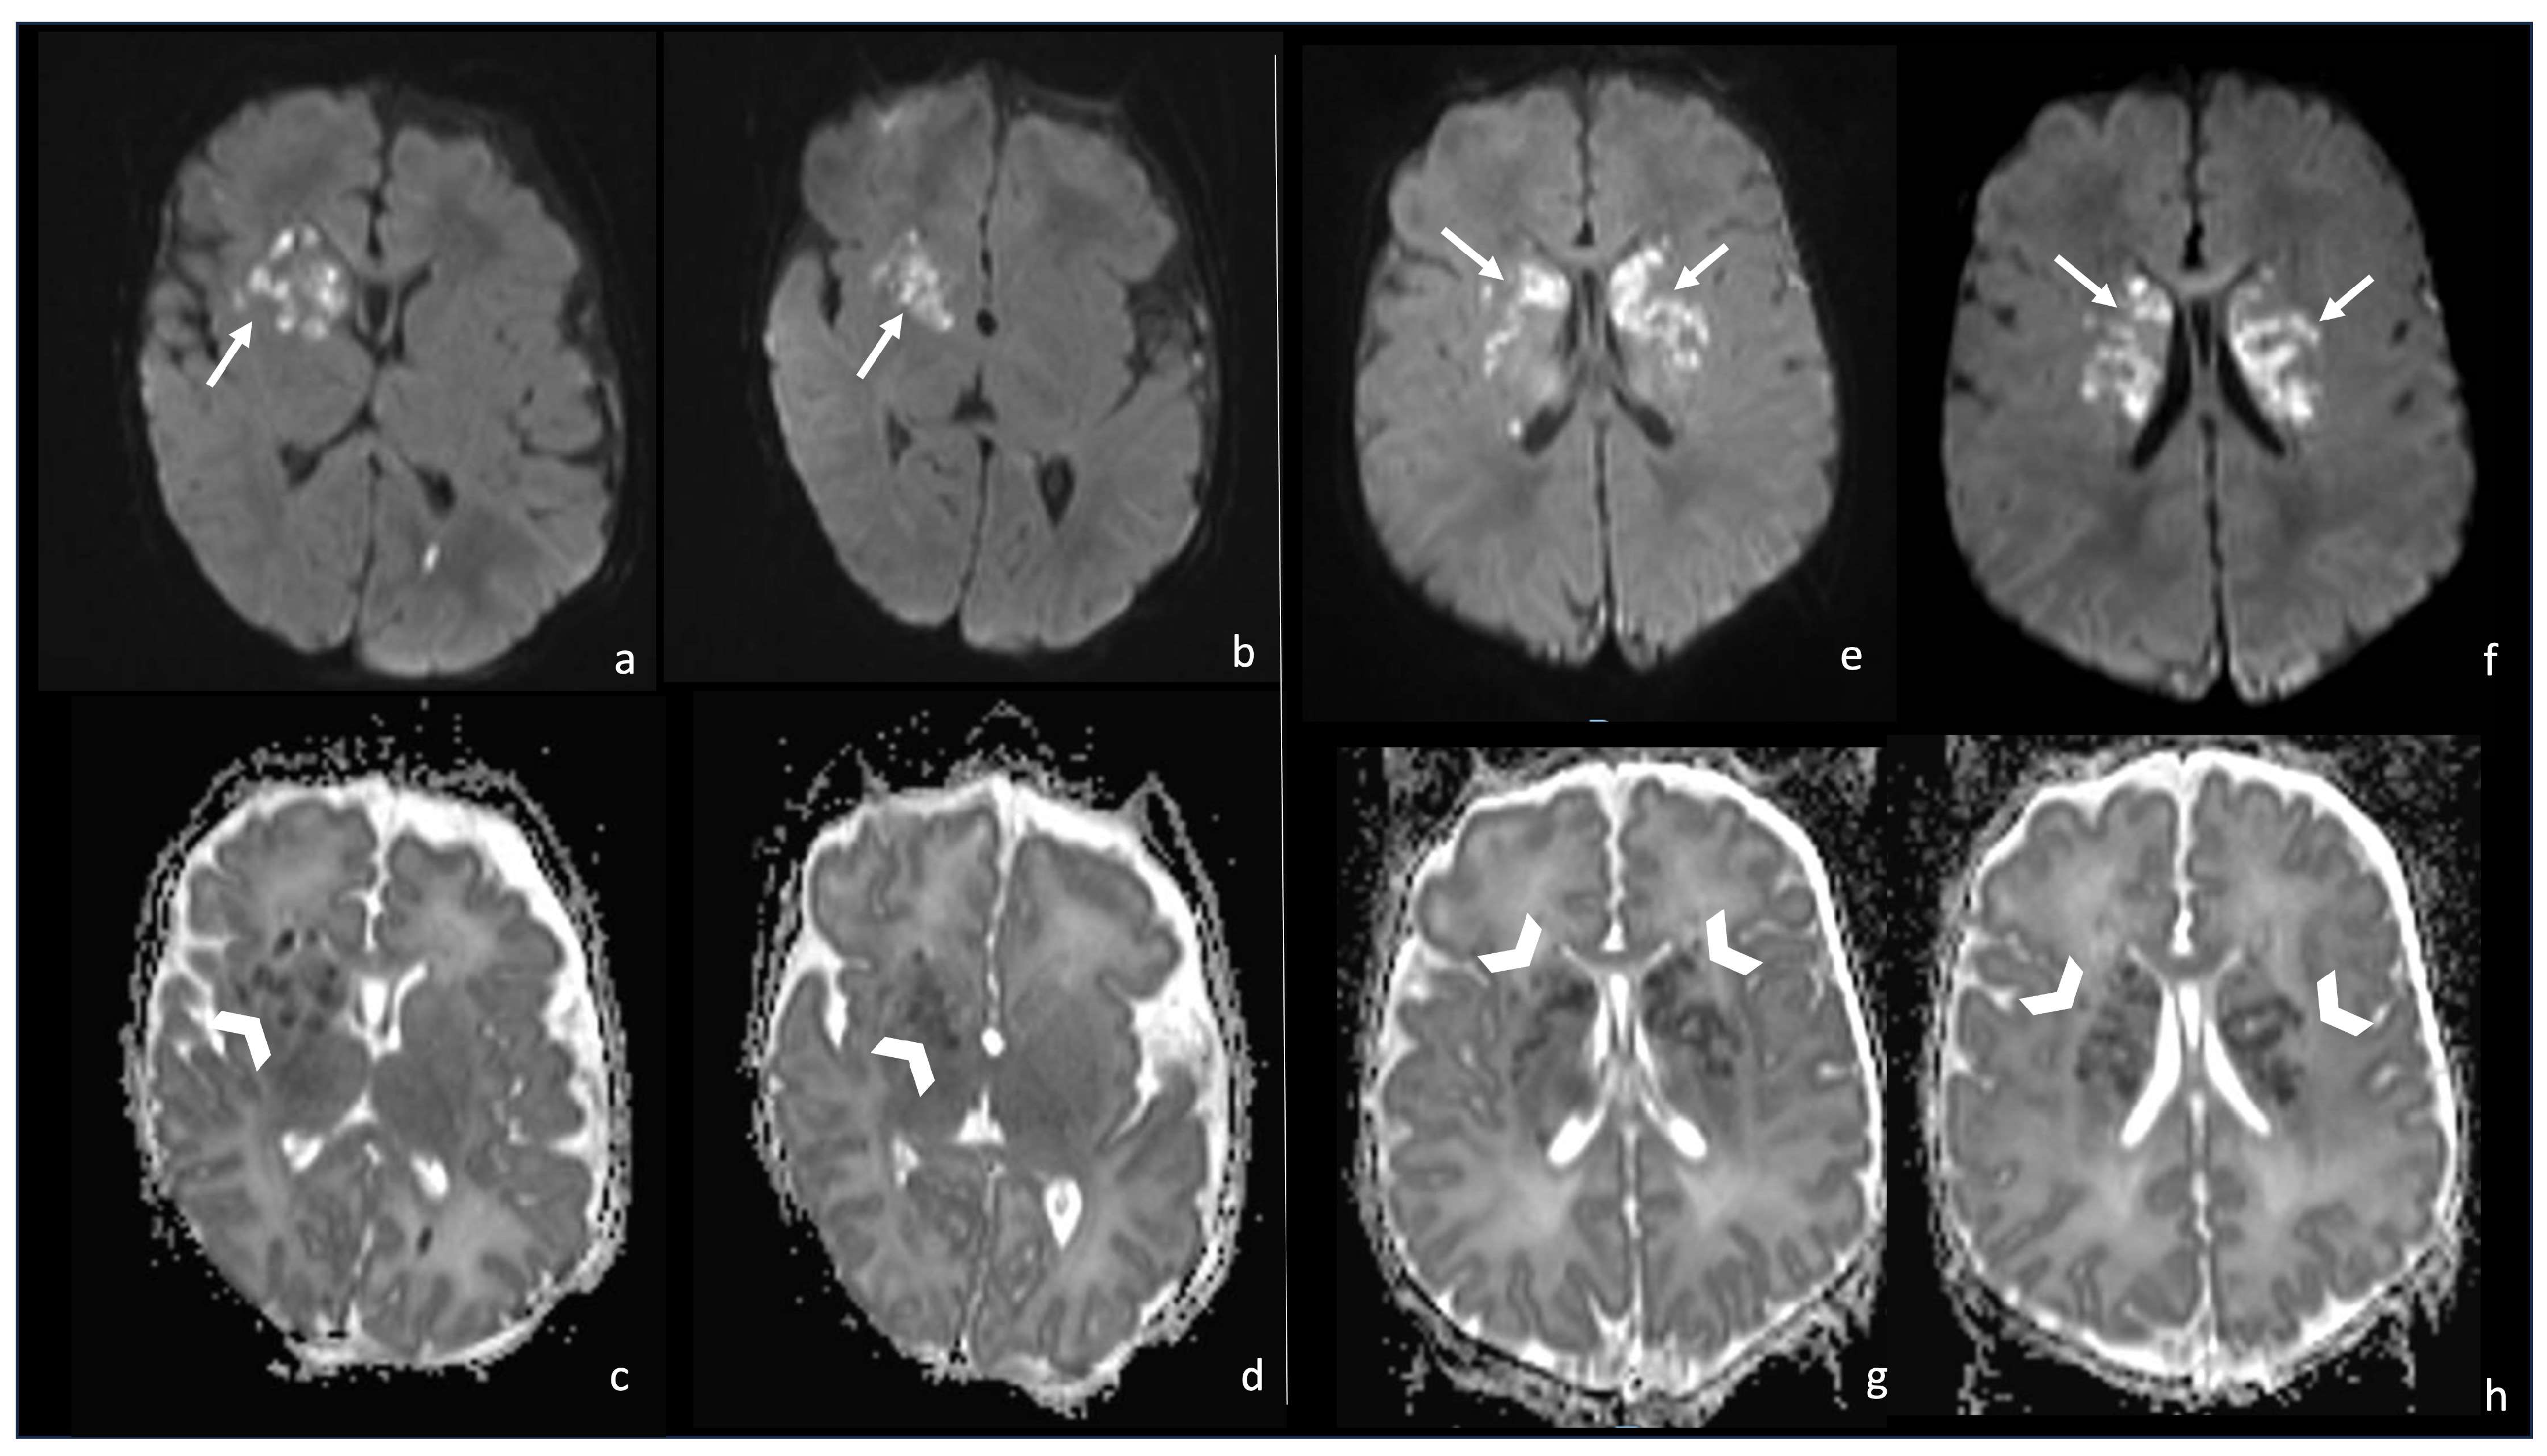

6.1. Cerebritis and Abscesses

- Early cerebritis stage (3–5 days): Bacteria infiltrate the vessels causing vessel wall inflammation and vessel necrosis, which lead to blood barrier disruption and parenchymal invasion. The resulting cerebral infection, namely the early cerebritis, is limited to a focal portion of the brain, does not present a capsule, and presents a coexisting edema. In MRI, early cerebritis is seen as an inhomogeneous and ill-defined area of hyperintensity on T2WI and hypointensity on T1WI, surrounded by edema appearing hypointense on T1WI and hyperintense on T2WI. It presents a diffusion restriction on DWI/ADC in relation to cytotoxic edema and inflammatory hypercellularity. Hemorrhagic foci present as T1WI hyperintense areas within the lesion. After contrast administration, a patchy enhancement is observed, yet no capsule may be identified. On the US, early cerebritis appears as an ill-defined area of inhomogeneous echogenicity presenting increased vascularity on Transcranial Doppler, pairing CT findings, with an ill-defined area of inhomogeneous hypodensity with inhomogeneous and patchy enhancement.

- Late cerebritis (5–14 days): Cerebritis progressively evolves to show a necrotic core and an initial encapsulation. This stage flows into and partly overlaps with the early capsule stage since this last represents a progression with similar, yet more advanced features of the late cerebritis stage. In MRI, the late cerebritis results in a focal formation characterized by a necrotic core, appearing inhomogeneous on both T1 and T2WI, without a complete and regular contrast peripheral enhancement, yet with a defined diffusion restriction on DWI/ADC. On the US, the appearance is similar to the early cerebritis, yet the lesion appears more focal and the core starts becoming hypoechogenic, similar to CT showing a significantly hypodense core in the lesion with irregular and incomplete peripheral enhancement. Early capsule formation (14–30 days): The cerebritis is becoming an abscess since the capsule is evident, yet it is incomplete and thin and appears as a hyperintense rim on T1WI and a hypointense rim on T2WI with contrast enhancement on T1WI.

- Early capsule formation (2 weeks to 2 months): the lesion presents diffusion restriction on DWI/ADC, mainly in relation to hypercellularity. Sonographically, the lesion presents a well-defined hypoechoic core and an incomplete hyperechoic rim. CT shows a well-defined hypodense core and an incomplete peripheral enhancement.

- Late capsule formation (weeks to months): The parenchymal abscess presents a necrotic core, appearing hypointense on T1WI and hyperintense on T2WI with diffusion restriction on DWI/ADC. The capsule is inhomogeneously thick, appearing thicker towards the cortex and thinner towards the ventricles, appears isointense on T1WI and hypointense on T2WI, and presents an intense enhancement. On the US, the abscess presents a well-defined hypoechoic core and a complete hyperechoic rim, pairing CT that shows a well-defined hypodense core and a complete peripheral enhancement.

6.2. Infarcts